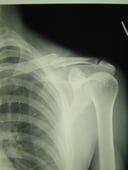

●右鎖骨骨折

当患者さんは手術療法に強く抵抗があり当院での保存療法を選択されました。

骨折部位の短縮転移があたので整復操作が必須になります。運よく短縮転移が矯正されたので保存療法で経過をみました。暑い時期だったので来院の度に固定を外し体を清拭して施術後、新しい下着の上から再度固定をする運びになりました。

骨折部位には超音波、患部以外の所は関節運動、経過を見て軽いマッサージを開始。固定も少しずつ簡易な物へ変更し二カ月後には三角巾のみ、三ヵ月経過すると肩関節の挙上もできるようになりました。

経過良好で完治しました。

左のレントゲンは短縮転位 (受傷時) 右は整復操作をして骨片が重なり合っている状態